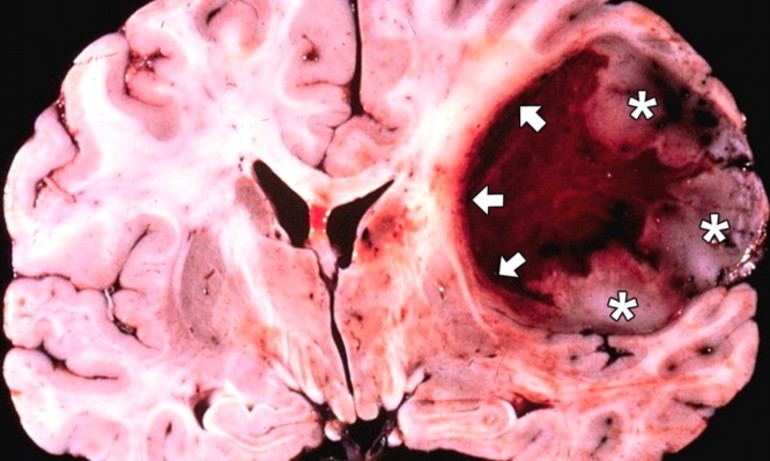

| Геморрагический инсульт | Разрыв аневризмы, артериовенозная мальформация, артериальная гипертензия, прием антикоагулянтов, травма головы | Внезапная сильная головная боль («самая сильная в жизни»), тошнота, рвота, потеря сознания, судороги, очаговая неврологическая симптоматика (слабость, онемение) | Хирургическое вмешательство (клипирование аневризмы, удаление гематомы), контроль артериального давления, симптоматическая терапия, реабилитация |

- Кровоизлияние в мозг: при высоком артериальном давлении может произойти разрыв узкого сосуда, что приводит к попаданию крови в мозговые ткани и воспалению. В большинстве случаев это заканчивается смертью.

Аневризма и ее симптомы

Аневризма представляет собой расширение артерии или вены, образующее мешковидное образование, заполненное кровью. Чаще всего данное заболевание локализуется в области основания черепа. Опасность аневризмы заключается в высокой вероятности разрыва ее тонкой стенки, что может привести к кровоизлиянию. Если аневризма небольшого размера, риск разрыва значительно снижается.

Причинами возникновения аневризмы могут быть различные приобретенные заболевания, такие как опухоли, инфекции или травмы головы. Однако чаще всего она развивается из-за нарушений в синтезе коллагена, что приводит к образованию слабых стенок сосудов.